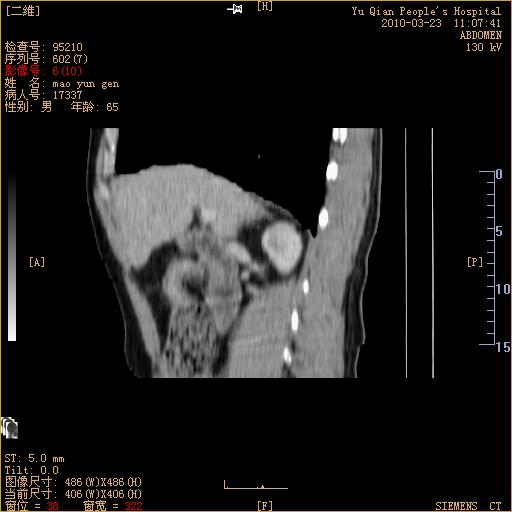

标题: CT25266:消瘦月余,前来肝部检查,请看看肠腔 [打印本页]

标题: CT25266:消瘦月余,前来肝部检查,请看看肠腔

肝区结肠占位,腺癌可考虑,建议肠镜活检。

升结肠肠壁增厚,不均强化,考虑升结肠腺癌可能性,建议肠镜检查。

1)考虑升结肠癌。2)右肾小囊肿。